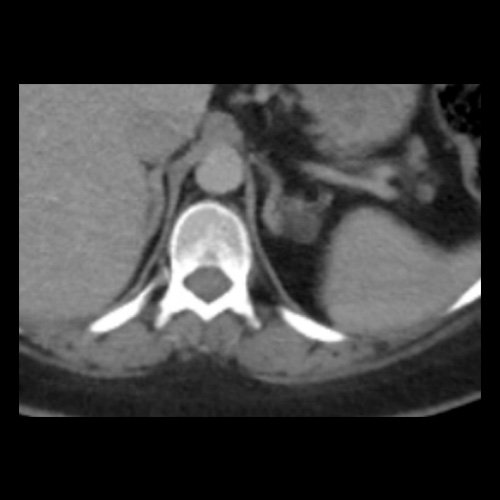

TC de abdomen y pelvis con contraste endovenoso (12/02/2026) Corte axial: adenoma adrenal izquierdo de 16 mm.

• Tomografía de abdomen y pelvis sin contraste oral con contraste EV (12/02/26):  El hígado es de forma, tamaño y situación habituales. Su superficie es lisa, y sus bordes son agudos. Imagen hipovascular aislada de 15 mm en segmento V de aspecto inespecífico. Sugiero complementar con RMI. La vía biliar intra y extrahepática es de calibre conservado. La vesícula biliar es de forma, tamaño y situación normales, sin imágenes que sugieran la presencia de litiasis. Tener en cuenta que este método puede pasar por alto litiasis colesterínicas. El bazo es de forma, tamaño y situación normales. El páncreas es de características normales. El conducto de Wirsung es de calibre conservado. Adenoma adrenal izquierdo de 16 mm. Ambos riñones son de forma, tamaño y situación habituales. Concentran y eliminan adecuadamente la sustancia de contraste. Sin evidencia de alteraciones calicopiélicas ni ureterales. La aorta, las arterias ilíacas primitivas, internas, externas y femorales, son de calibre y trayecto conservado, permeables. La vena cava inferior y las venas ilíacas primitivas, internas, externas y femorales son de calibre y trayectoria conservados, permeables. No se observan adenomegalias intraperitoneales, retroperitoneales, ilíacas ni inguinales. No se observan alteraciones a nivel del tracto gastrointestinal. La vejiga es de paredes lisas, sin presentar efectos de masa endoluminales ni parietales. Utero en AVF, lateralizado a izquierda. Pequeña hernia umbilical de contenido graso y escaso líquido intrasacro. No se identifican alteraciones en las estructuras óseas visualizadas.